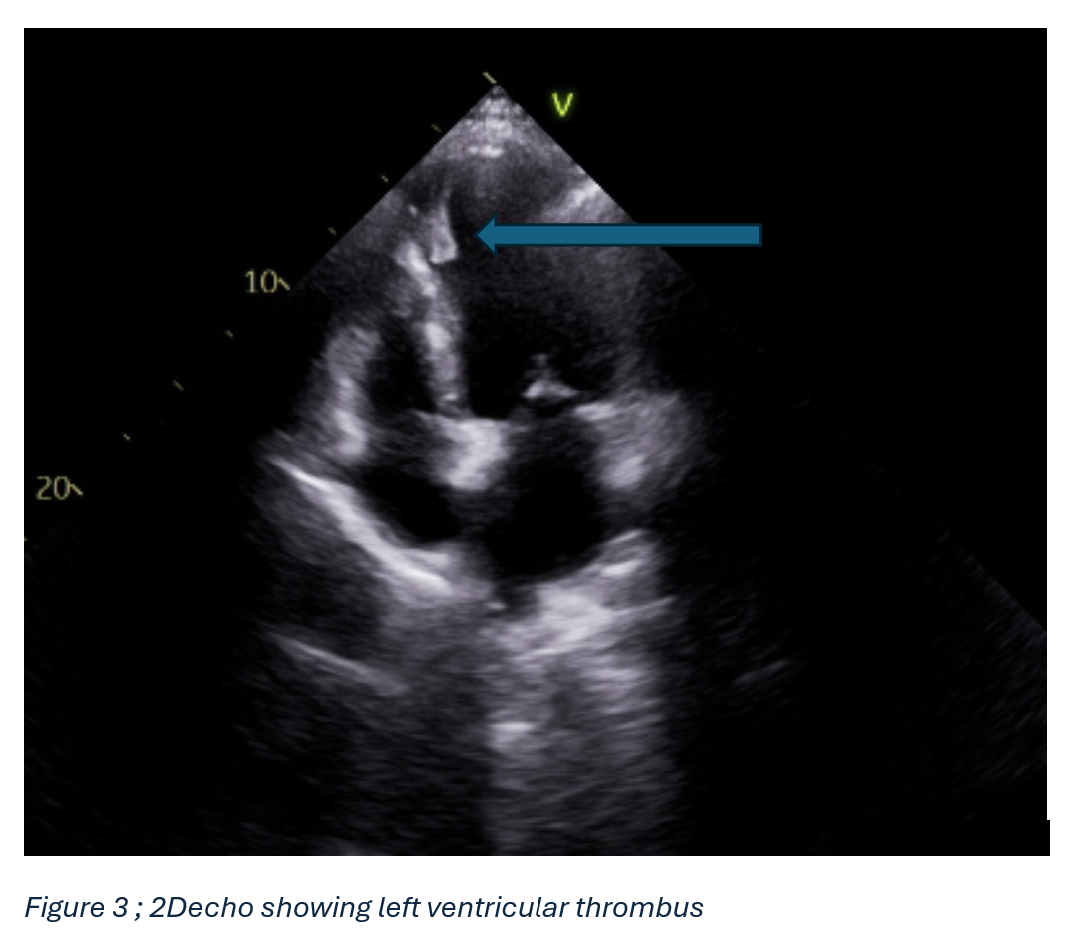

Echocardiography revealed severe global hypokinesis with an ejection fraction (EF) of 20–25% and an apical LV mural thrombus (2.8 × 1.2 cm). The cardiomyopathy was attributed to a combination of sepsis-related myocardial dysfunction and possible tachycardia-induced cardiomyopathy. He was managed with intravenous fluids, vasopressors, azithromycin, and anticoagulation (enoxaparin transitioning to apixaban).

Discussion: Legionella pneumophila can lead to rare but serious cardiac complications, including myocarditis, endocarditis, and LV thrombus, due to bacterial invasion, inflammation, and sepsis-related dysfunction. In this case, reduced ejection fraction and severe hypokinesis resulted in a 2.8 × 1.2 cm LV thrombus, worsened by atrial flutter and tachycardia-induced cardiomyopathy. Effective management required coordinated anticoagulation and infection control. Legionnaires’ disease, often linked to contaminated water systems, is notifiable due to its outbreak risk. Early cardiac evaluation and prompt treatment are critical for improving outcomes in cases with cardiac involvement.